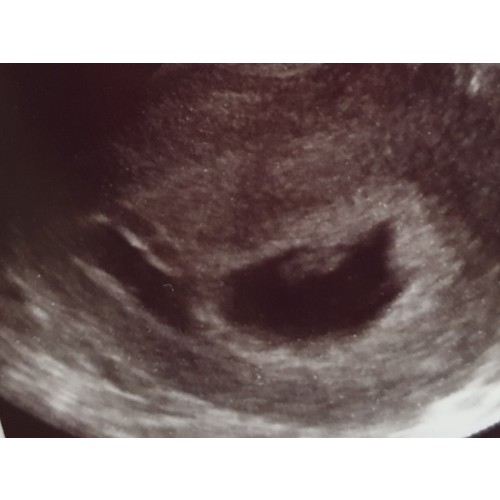

Dit was 6+4 net een uitwendige echo. Baarmoeder, vruchtje, dooierzakje, hartje, alles was te zien. Ik was ook heeeeeel zenuwachtig. We gingen van het ergste uit. Maar toen zette ze dat echo-ding op m'n buik en gelijk zagen we dit beeld en toen wisten we dat het goed zat. Succes!

Hier precies 6 weken zwanger, mooi knipper lichtje te zien, wat net begonnen was met kloppen! 😍

Mijn precies 6 weken echo....mooi om het hartje te zien kloppen.....helemaal happy😁

Hier 6 + 3 weken, mooi kloppend hartje. Kleine spruit is nog niet heel fotogeniek😜